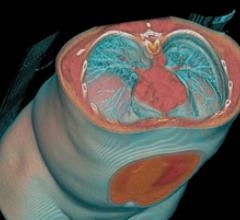

Contributing Editor Greg Freiherr offers an overview of computed tomography (CT) advances at the Radiological Society of North America (RSNA) 2015. The video includes Freiherr during his booth tours with some of the key vendors who were featuring new technology.

Computed Tomography (CT)